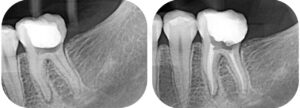

Nas imagens a seguir apresentamos casos: à esquerda, o dente com infecção. À direita, após o tratamento de canal, o dente tratado e preservado (imagem radiopacas mais claras/brancas dentro dos condutos dos canais).